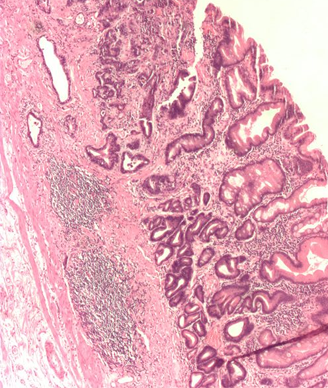

Gastric adenocarcinoma with poor-moderate differentiation; copyright 2009 Nephron.